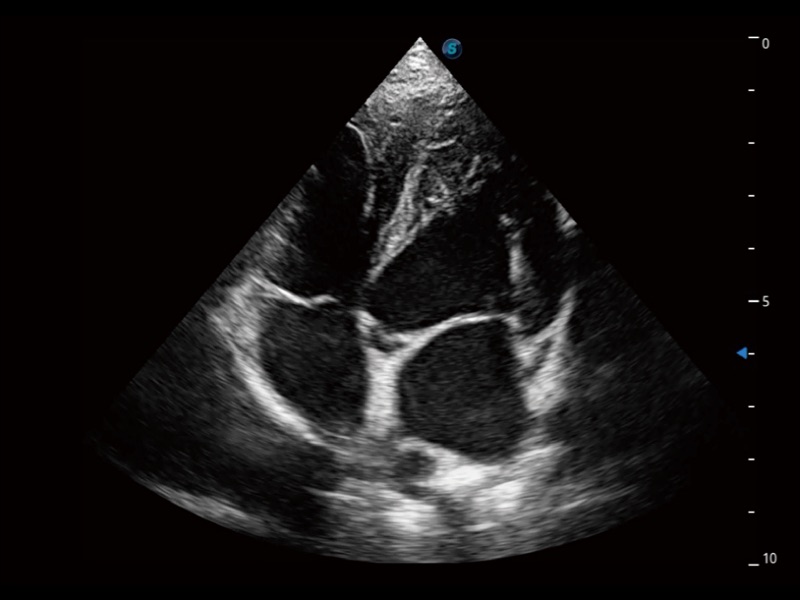

通过360度任意调节3条M型取样线,在同一心动周期上观察心脏不同位置的运动曲线,得到准确的心功能测量数据,有效评估心肌运动及左心室功能。

为精细结构及组织边缘提供高清晰度的图像和更大的成像视野。帮助减轻医生的用眼疲劳,快速精准获得测量的数据。